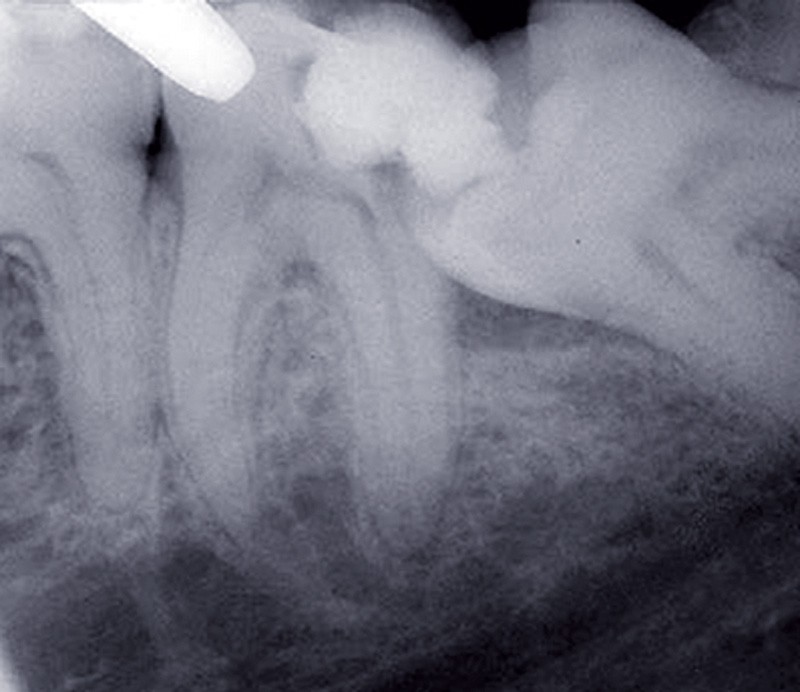

Lésion carieuse de la dent de sagesse et/ou de la deuxième molaire adjacente

Ces lésions sont d’autant plus probables que la dent de sagesse est en situation mésioversée et bloquée par la 2e molaire (fig. 3). L’appui continu de la couronne de la 3e molaire sur la face distale de la 2e peut provoquer des lésions carieuses du collet ou de la couronne, une rhizalyse ou conduire à la mortification.